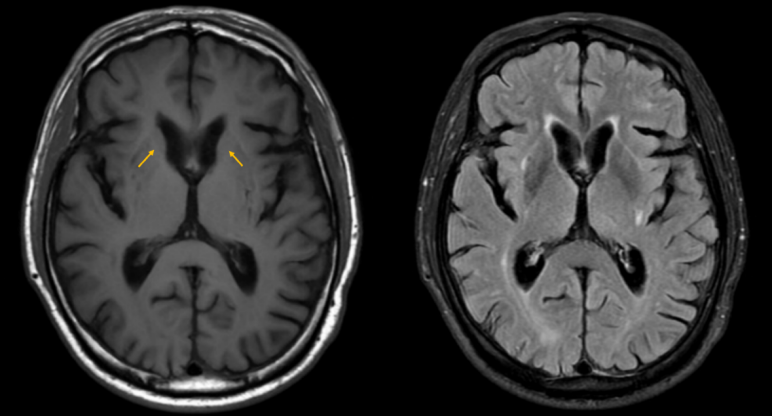

• 头颅MRI+磁敏感加权成像(SWI):双侧尾状核头萎缩(图3)。

图3 头颅MRI+SWI:双侧尾状核头萎缩(左T1相,右FLAIR相)